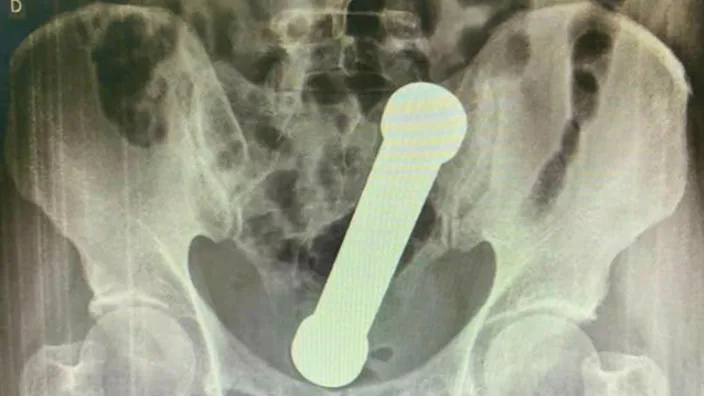

After X-rays were conducted, doctors found the 20cm -long-dumbbell wedged in where the colon meets the rectum. Ya can't miss it.